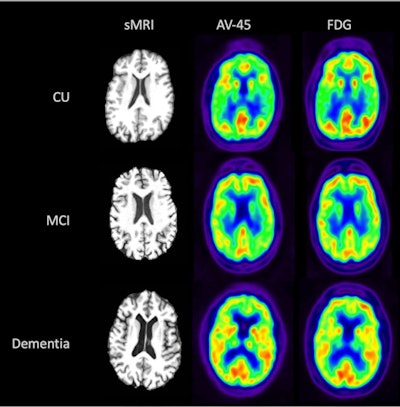

In this study, the researchers investigated to what extent the information captured in early frames of amyloid PET scans compared to that of F-18 FDG PET scans among cognitively unimpaired patients (CU), patients with mild cognitive impairment (MCI), or patients with dementia.

Visual comparison of sMRI, early-frame F-18 florbetapir, and F-18 FDG-PET for participants from each disease state (CU, MCI, and dementia). Image courtesy of the Journal of Hybrid Imaging.The partial correlation of early-frame F-18 florbetapir with F-18 FDG was significant in all 84 brain ROIs, with correlation values ranging from 0.61 to 0.94, the researchers found. The highest correlation between the early-frame F-18 florbetapir and F-18 FDG data within cortical regions was in the anterior temporal lobe (left: r = 0.85, p < 2e-16; right: r = 0.85, p < 2e-16).